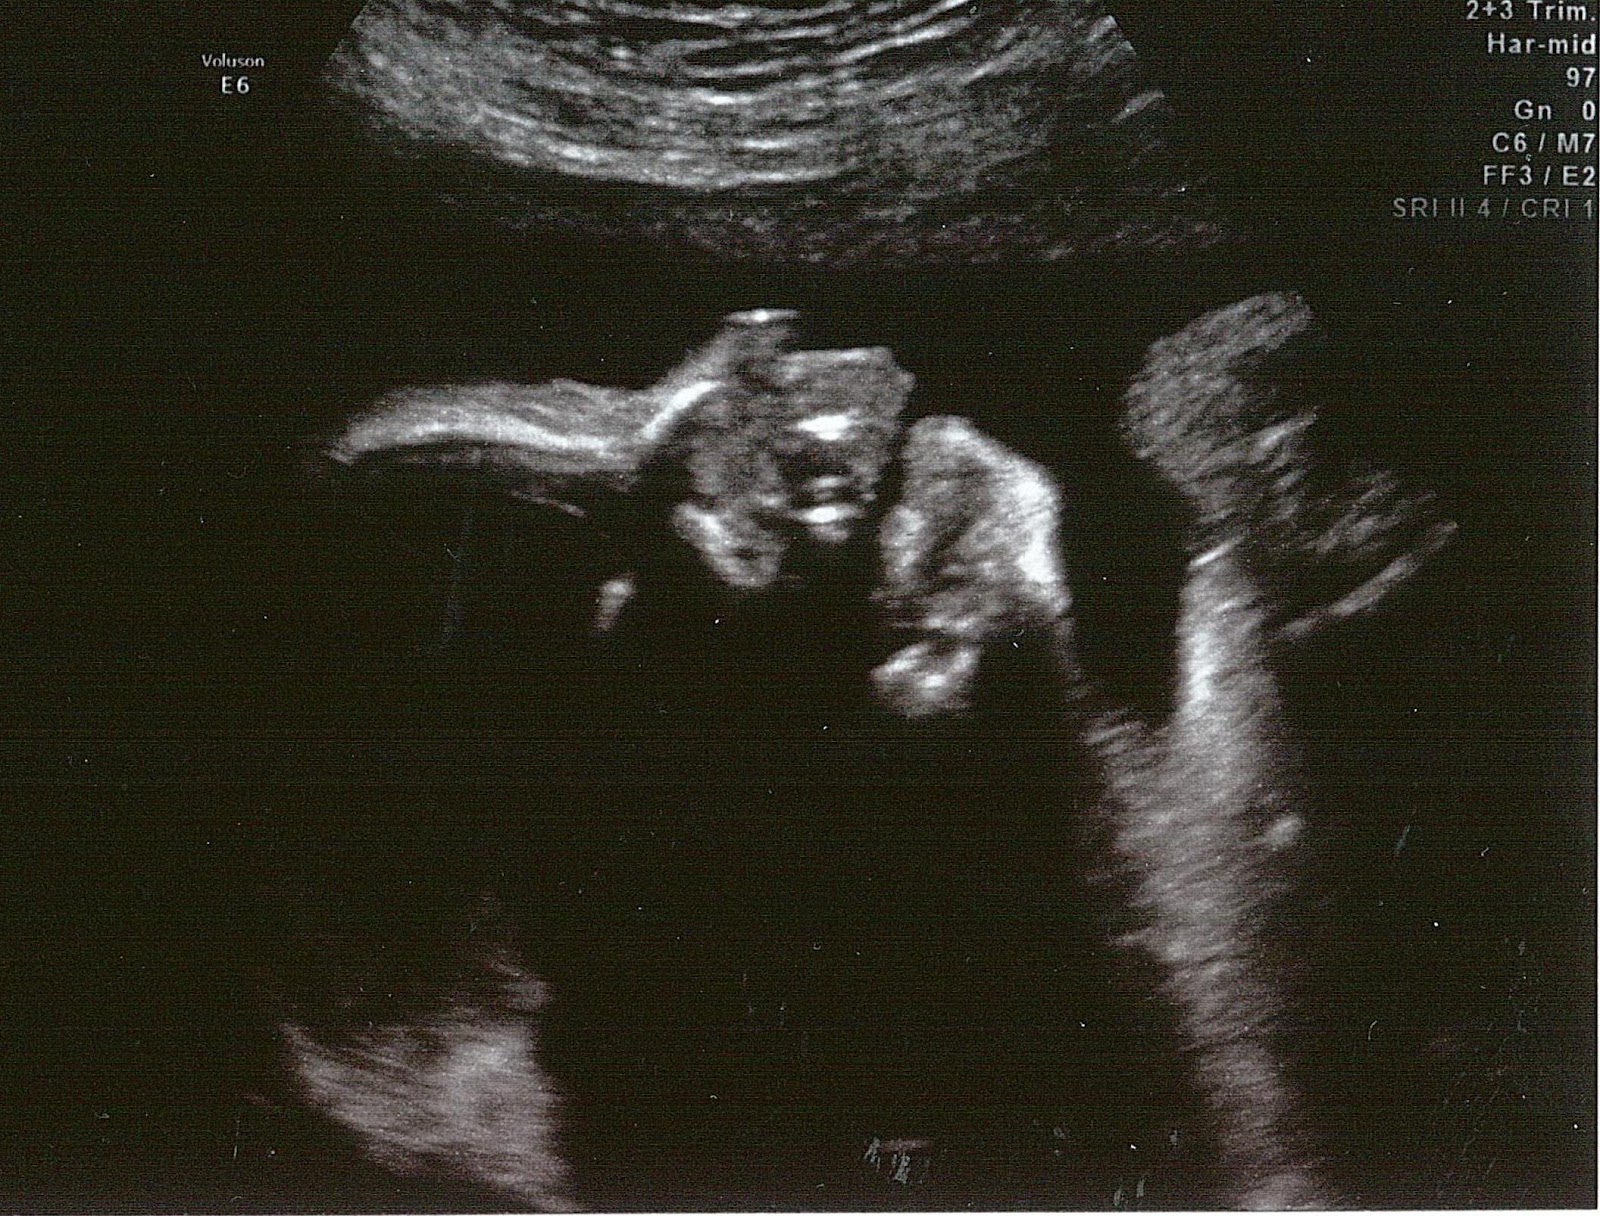

Here are the pictures of the cutest little boy ever (I'm sure you'll agree...)! :)

It's so crazy - he looks like he's full term and ready to come out and meet us, but he's only 26 weeks 2 days here!

I LOVE his little face! I started freaking out about how cute he is when the dr pulled up the 3D screen. My mom and I were both squealing the whole 8-minute scan! lol

We saw him do a few cool things - As you can see in the 2D pic, his mouth is open - this was in the middle of us watching him eat and swallow. We also saw him kicking me! And the crazy part was that I could feel him doing it as I watched! I always wonder what he's doing in there when I feel movement - so that was cool to see!

I thought he'd be pretty squished in there by now, but he was sitting (breech) on my bladder with his head on my top left and his legs at a 90 degree angle on my bottom right. We watched him pick his feet up and stomp back down on me, like he was trying to walk somewhere. He didn't get anywhere fast... And I'm glad it's not painful yet! :)